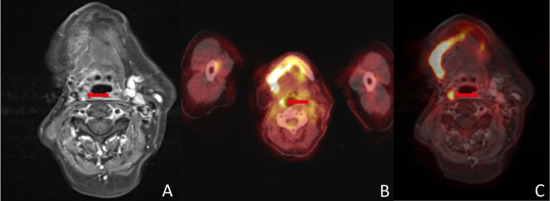

Figure 3.

(A) Size and contrast enhancement in MRI were misleading in this histopathologically negative neck. Absence of FDG uptake led to correct negative results in (B) PET/CT and (C) PET/MRI. A combination of different modalities, image fusion in particular, can improve the assessment of cervical lymph nodes. Red arrows point to the region of interest in all three imaging modalities.

MRI indicated LNM in two (5.4%) histologically negative patients. PET/CT was false positive in one (2.7%) patient and PET/MR did not depict any false positive neck findings (see Figure 3). In seven (18.9%) patients with divergent results between imaging methods, one did not show an elevated risk of LNM in histology.

Both MRI and FDG-PET/CT have proven to have good diagnostic accuracy for detecting LNM in HNC in previous investigations [6,17,26,27,28,29]. Studies investigating the simultaneous use of MRI and PET have shown promising results in terms of diagnostic accuracy for detecting cervical LNMs [5,6,30,31]. To determine the clinical value of PET/MRI fusion, we compared the results of MRI, PET/CT and PET/MRI in patients with HNC. All patients received MRI and PET/CT on the same day and surgery afterwards. Histopathological results served as the gold standard. MR images and PET data were merged retrospectively for research purposes only. To the best of our knowledge, this study is the first to investigate the diagnostic accuracy of retrospectively fused PET/MRI in a cohort of this size at a single center. The results are consistent with existing data regarding the diagnostic accuracy of MRI and PET/CT. From a clinical perspective, a reduction in false negative results is particularly desirable [6]. Unfortunately, data from the present investigation did not demonstrate evidence in this direction for any of the examined modalities. Although PET/MRI did not show any false positive results in our data, false negatives were as high as in MRI and PET/CT. In our cohort, at least one modality showed a false negative result in seven (18.9%) patients. In this context, a combination of modalities could be beneficial as there were only two (5.4%) patients where all modalities showed a false negative result. However, we do not suggest omitting neck dissection based solely on imaging findings. Nonetheless, in selected cases with high intraoperative risk, a combination of different imaging modalities is favorable for guiding therapeutic decisions (see Figure 3).